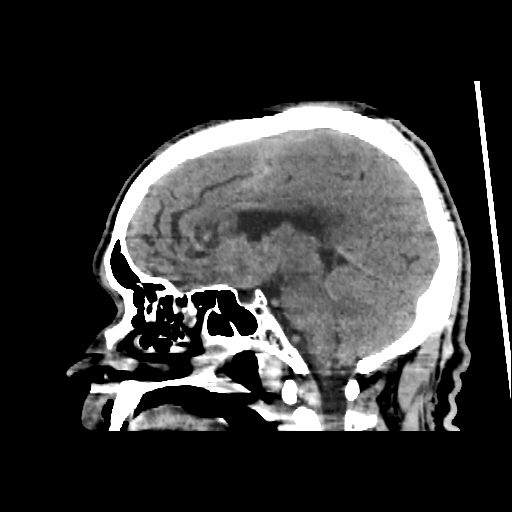

A 60 years old man with seizure since 12 years

Plan CT scan was done on 22 march 2016